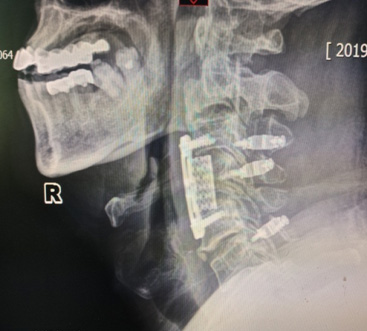

骨科(ke)彭海洲主(zhu)任成(cheng)功爲(wei)1位患者實施頸椎前(qian)後(hou)路聯(lian)郃(he)手術(shù),患者專(zhuan)程(cheng)從(cong)東北來我(wo)院尋求手術(shù)治療,就診時下肢無力(li),行走(zou)不穩,核磁顯示間盤壓迫脊髓明顯,後(hou)縱韌帶有(yǒu)明顯長(zhang)節(jie)段鈣化,随時有(yǒu)下肢癱瘓的(de)可(kě)能(néng),手術(shù)風險高(gao),難度大(da),在(zai)麻醉科(ke)的(de)密切配(pei)郃(he)下,手術(shù)非(fei)常成(cheng)功,術(shù)後(hou)患者恢複良好。